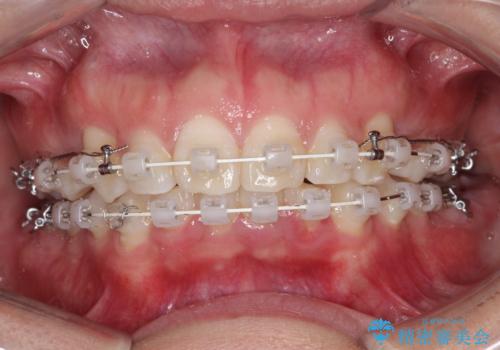

- 矯正装置

- 審美装置

- 治療期間

- 2年3ヶ月

上の歯の前から4番目の歯を2本抜歯して、そのスペースに前歯を移動させて、前歯を引っ込める計画としました。